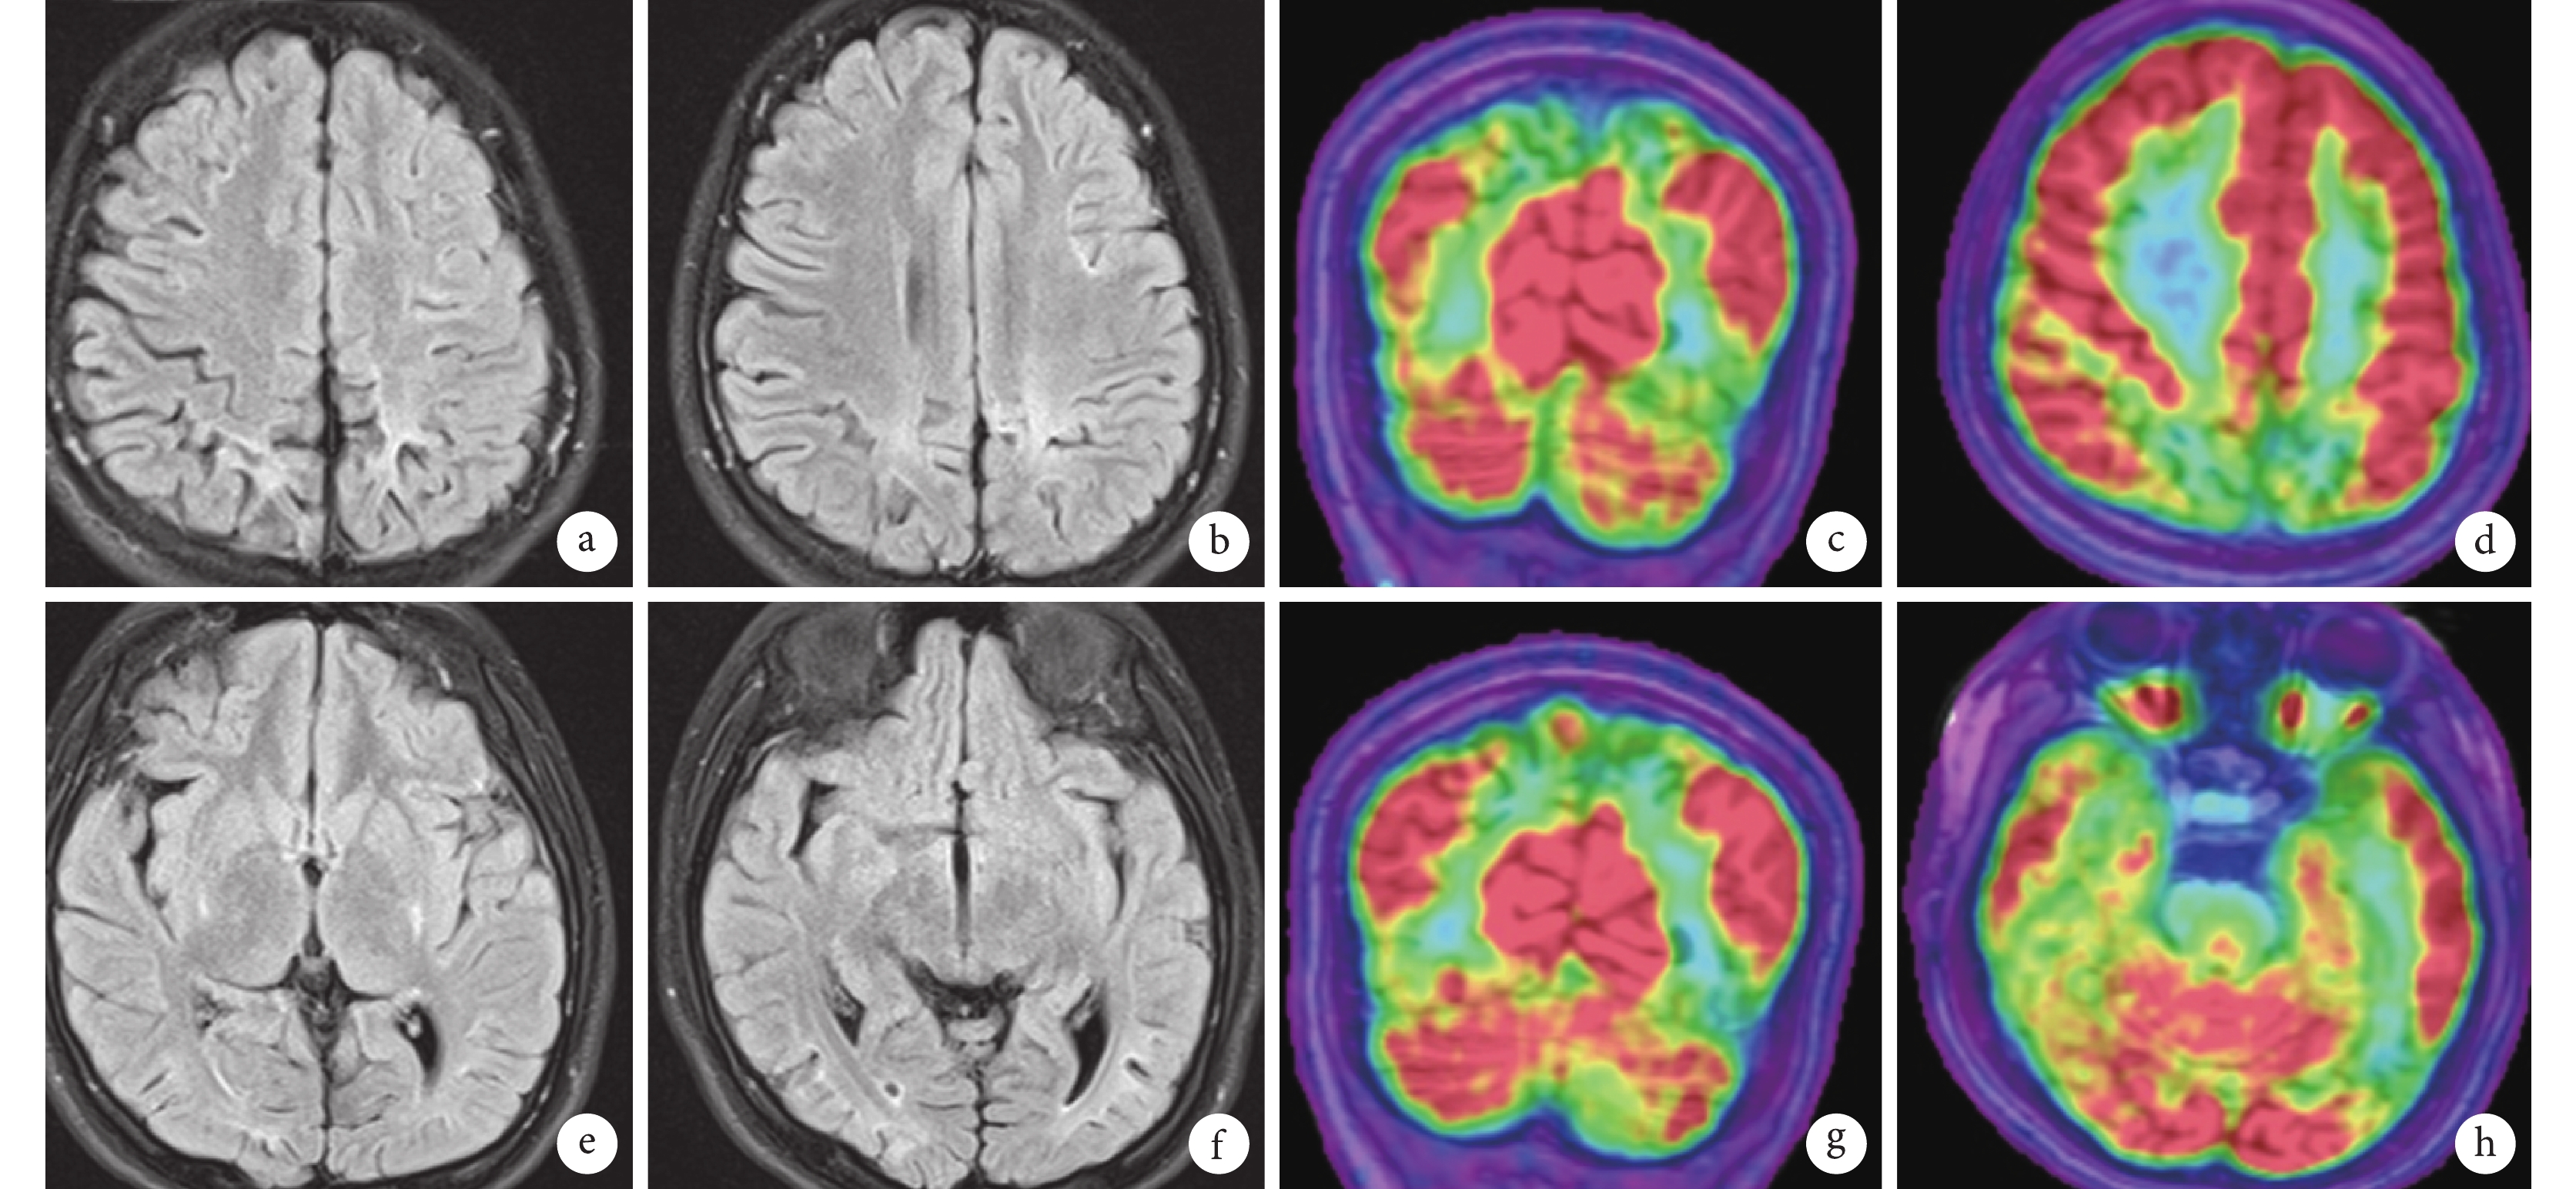

1.3 影像學

患者頭顱核磁共振成像(MRI)表現為 Flair 像雙側頂、枕及后顳高信號及局部腦萎縮。18F-2-氟-2-脫氧-D-葡萄糖-正電子發射計算機斷層顯像(18FDG-PET-CT)表現為雙側頂、枕、后顳代謝減低(圖 4)。

圖4

患者影像學檢查 MRI 顯示雙側枕及顳后異常信號及局部腦萎縮;MRI-PET 融合可見相應部位低代謝

Figure4.

MRI showed abnormal signals and brain atrophy in bilateral temporal and occipital regions. MRI-PET fusion showed low metabolism at corresponding area